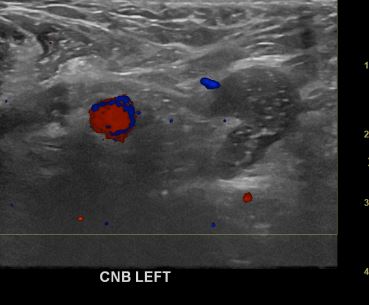

아산유외과개원후 651번째 전이암진단

상기환자 외부검사상 이상소견으로 내원하신 60대여성으로 겨드랑이 림프절에 전이된 의심부분 조직검사하여 유방암진단되었습니다.